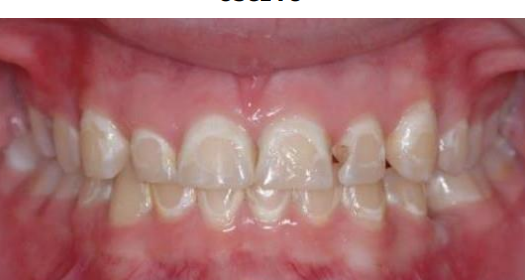

MFD EXAMS /23 6 1234567891011121314151617181920212223 You have 30 min to complete this exam. The timer will start once you begin Attention: Only a few minutes left! Please submit your answers soon. MFD 1 Get a quick sneak peek before the real exam !This trial quiz is designed to show you the question style, difficulty level, and how the options will appear on the platform. 1 / 23 1. What is the lethal dose and toxic dose of fluoride, management? Check 2 / 23 2. What the advantage of silver diamine over other methods and disadvantages ? Check 3 / 23 3. Method of topical fluoride application with concentration ? Check 4 / 23 4. What will happen if left untreated? Check 5 / 23 5. What changes that will happen if the habit stopped? Check 6 / 23 6. Give 3 of your initial stage of treatment? Check 7 / 23 7. What are the causes? Check 8 / 23 8. What is this? Check 9 / 23 9. Then they specified the type of pain and asked about the diagnosis Check 10 / 23 10. What other tests to check vitality of the pulp? Check 11 / 23 11. What are the factors will govern the Rx of Posterior cross bite ? Check 12 / 23 12. What are the factors that govern the treatment of anterior cross bite? Check 13 / 23 13. Name the appliance that you can use to treat this case? Check 14 / 23 14. Name 3 causes? Check 15 / 23 15. Name the most important clinical diagnostic information you need to know. (check RCSI intensive course )? Check 16 / 23 16. What do you see? Check 17 / 23 17. What is your treatment? Check 18 / 23 18. Name the investigations needed? Check 19 / 23 19. causes for gingival enlargement ? Check 20 / 23 20. What is the common side effect of this drug? Check 21 / 23 21. Name the drug that he may take to treat this condition? Check 22 / 23 22. The patient may have what? Check 23 / 23 23. What is this clinical condition? Check /31 2 12345678910111213141516171819202122232425262728293031 You have 30 min to complete this exam. The timer will start once you begin Attention: Only a few minutes left! Please submit your answers soon. MFD 2 Get a quick sneak peek before the real exam !This trial quiz is designed to show you the question style, difficulty level, and how the options will appear on the platform. 1 / 31 1. Mention 2 fixed space maintainers and 2 removable space maintainers other from mentioned : Check 2 / 31 2. Other space maintenance used for child lost primary second molar E before the eruption of the permanent molars ? Check 3 / 31 3. What are the difference between nance appliance and Transpalatal arch Check 4 / 31 4. What material used to attach band? Check 5 / 31 5. What instruction you give to patient? Check 6 / 31 6. Name other fixed space maintainer used in upper jaw and mechanism of their action? Check 7 / 31 7. What component of this appliance? Check 8 / 31 8. What is this appliance , for what its used ? Check 9 / 31 9. Treatment? Check 10 / 31 10. Define Abrasion and Erosion? Check 11 / 31 11. What does this picture show? Check 12 / 31 12. what investigations you can do ? Check 13 / 31 13. Drugs can lead to lichenoid reaction Check 14 / 31 14. What extra oral features in “ Lichenoid reaction )? Check 15 / 31 15. What microscopical features of it ( licheonoid reaction )? Check 16 / 31 16. Definitive diagnosis ? Check 17 / 31 17. Mention type of suggested biopsy ? Check 18 / 31 18. Mention 4 differential diagnosis ? Check 19 / 31 19. Mention 4 questions you will ask the patient ? Check 20 / 31 20. Give 4 intraoral decription of what you see ? Check 21 / 31 21. What the other surgery can be performed to make prothesis? Check 22 / 31 22. Can this tooth stand with fixed prothesis? (in the opg )à taken from Malek file ? Check 23 / 31 23. Radiograph of missing multiple teeth consider it according to Antes law? ON which tooth you will make Abutment ? Check 24 / 31 24. What is Antes law? Check 25 / 31 25. What is best one to use as abutment in fixed prosthesis A or B? Check 26 / 31 26. What relevance of this picture? Check 27 / 31 27. What’s complication of doing surgery in this area floor of mouth? Check 28 / 31 28. Other 2 radiograph needed in diagnosis? Check 29 / 31 29. Give 4 differential diagnosis? Check 30 / 31 30. What can you see ? Check 31 / 31 31. What is the name of radiograph? Check Your score is /30 1 123456789101112131415161718192021222324252627282930 You have 30 min to complete this exam. The timer will start once you begin Attention: Only a few minutes left! Please submit your answers soon. MFD 3 Get a quick sneak peek before the real exam !This trial quiz is designed to show you the question style, difficulty level, and how the options will appear on the platform. 1 / 30 1. Treatment? Check 2 / 30 2. Histopathology? Check 3 / 30 3. Differential diagnosis Check 4 / 30 4. Clinical features’? Check 5 / 30 5. Patient said, this lesion is very frequent, why? Check 6 / 30 6. What are the causes for ulcers? Check 7 / 30 7. Patient have other signs like uveitis ,Genital ulcerations which syndrome he had ? Check 8 / 30 8. Name of the lesion ? Check 9 / 30 9. Mention some TMJ movement ? Check 10 / 30 10. Blood supply ? Check 11 / 30 11. Nerve supply ? Check 12 / 30 12. Which muscles close? Check 13 / 30 13. Action of open and open wide? Check 14 / 30 14. Why it’s Atypical joint ? Check 15 / 30 15. Name of the ligaments ? Check 16 / 30 16. What would be your management? Check 17 / 30 17. Bacteria involved Check 18 / 30 18. Which type of Periodontitis? Check 19 / 30 19. Treatment? Check 20 / 30 20. Histopathology? Check 21 / 30 21. Differential diagnosis? Check 22 / 30 22. Clinical features? Check 23 / 30 23. What are the time frames for making a complaint? Check 24 / 30 24. What are the 3 points related to negligence? Check 25 / 30 25. Who is allowed access to the patient records? Check 26 / 30 26. How to differentiate if it is upper or lower motor neuron lesion? Check 27 / 30 27. Management? Check 28 / 30 28. What are the causes? Check 29 / 30 29. What should you advise the patient to do? Check 30 / 30 30. What is this lesion? Check Your score is /24 1 123456789101112131415161718192021222324 You have 30 min to complete this exam. The timer will start once you begin Attention: Only a few minutes left! Please submit your answers soon. MFD 4 Get a quick sneak peek before the real exam !This trial quiz is designed to show you the question style, difficulty level, and how the options will appear on the platform. 1 / 24 1. What does MRONJ stands for? Check 2 / 24 2. Give definition for MRONJ Check 3 / 24 3. For what medical problems these medications are used? Check 4 / 24 4. Stages of MRONJ 3 Check 5 / 24 5. What’s this appliance? Check 6 / 24 6. At what age is it used? Check 7 / 24 7. What type of malocclusion is it used to treat? Check 8 / 24 8. What changes will produce? (4 options) Check 9 / 24 9. Disadvantages? Check 10 / 24 10. Why is it flabby tissue? Check 11 / 24 11. what is this condition called? Check 12 / 24 12. Causes ? Check 13 / 24 13. Clinical Features ? Check 14 / 24 14. How to avoid it ? Check 15 / 24 15. Management? Check 16 / 24 16. Ideal post length and width Check 17 / 24 17. Definition of Ferrule it’s the Check 18 / 24 18. What is the importance of the ferrule effect ? Check 19 / 24 19. Describe the radiolucency? Check 20 / 24 20. Give 6 differential diagnosis? Check 21 / 24 21. Give 5 radiographical features? Check 22 / 24 22. What is the difference between incisional and excisional biopsy? Check 23 / 24 23. What other 2 plain radiographs we can we can take? Check 24 / 24 24. ALARA? Check Your score is /22 1 12345678910111213141516171819202122 You have 30 min to complete this exam. The timer will start once you begin Attention: Only a few minutes left! Please submit your answers soon. MFD 5 Get a quick sneak peek before the real exam !This trial quiz is designed to show you the question style, difficulty level, and how the options will appear on the platform. 1 / 22 1. . Types of external root resorption? Check 2 / 22 2. The cause of root resorption in the pic? Check 3 / 22 3. How you will treat it? Check 4 / 22 4. What is this probe? Check 5 / 22 5. What is the mark a ? Check 6 / 22 6. What is the mark b ? Check 7 / 22 7. What is the score from the given reading? Check 8 / 22 8. What is the treatment need of the patient according to the score? Check 9 / 22 9. What is the differential diagnosis ? Check 10 / 22 10. Four clinical features of the lesion? Check 11 / 22 11. Treatment ? Check 12 / 22 12. Describe what do you see? Check 13 / 22 13. Causes for it ? Check 14 / 22 14. Treatment ? Check 15 / 22 15. Picture of patient with Anaphylaxis…after taking Check 16 / 22 16. What is diagnosis? - Check 17 / 22 17. What a the signs of Anaphyalxis reactions ? Check 18 / 22 18. What first line of treatment? Dose? Route of Adminstration? Check 19 / 22 19. Other drug used? Check 20 / 22 20. What are expected complications if not treated ? Check 21 / 22 21. What precautions should be made to prevent anaphylaxis reaction ? - Check 22 / 22 22. Name 10 drug in emergency used with their route of Administration and their condition they use in? Check Your score is /36 1 123456789101112131415161718192021222324252627282930313233343536 You have 30 min to complete this exam. The timer will start once you begin Attention: Only a few minutes left! Please submit your answers soon. MFD 6 Get a quick sneak peek before the real exam !This trial quiz is designed to show you the question style, difficulty level, and how the options will appear on the platform. 1 / 36 1. . What are cases that you have to extract the primary tooth? Check 2 / 36 2. D. What are the indications for extraction? Check 3 / 36 3. What are your treatment options? Check 4 / 36 4. Investigations? Check 5 / 36 5. Type of trauma? Check 6 / 36 6. Patient diagnosed with sjorgen syndrome Histology ? - Check 7 / 36 7. Patient diagnosed with sjorgen syndrome Mention four blood investigations ? Check 8 / 36 8. Patient diagnosed with sjorgen syndrome Mention two sites where can we take the biopsy Check 9 / 36 9. Patient diagnosed with sjorgen syndrome How can you differentiate between primary and secondary ? Check 10 / 36 10. Gingival inflammation present in which syndrome Check 11 / 36 11. What is the treatment? Check 12 / 36 12. mention another connective tissue disease that can lead to lesions “ intraorally “ similar to the Lichen planus ? Check 13 / 36 13. what serious complication can arise from Erosive lichen planus ? Check 14 / 36 14. If it was atrophic lesion what histology might be seen ? Check 15 / 36 15. List the histological features of lichen planus ? Check 16 / 36 16. Lichen planus what dose it affect? Check 17 / 36 17. Age group commonly affected ? -ref SAQ Check 18 / 36 18. What are the clinical presentation ‘ types of lichen planus ‘ Check 19 / 36 19. What might you see in patient’s body that has a relation to this lesion? Check 20 / 36 20. What are the differential diagnoses? Check 21 / 36 21. Factors for platelet adhesion? Check 22 / 36 22. What can you see? Check 23 / 36 23. Other 2 process of hemostasis? Check 24 / 36 24. Two diseases in which they increase ? Check 25 / 36 25. Two diseases in which they decrease? Check 26 / 36 26. Medical term when they decrease? And if they increased Check 27 / 36 27. Function Check 28 / 36 28. Life span ? Check 29 / 36 29. From where they arise? Check 30 / 36 30. Normal number? Check 31 / 36 31. What are the function of the guiding plane ? Check 32 / 36 32. The success rate ? Check 33 / 36 33. Mention single extra preparation requirement for Resin bonded bridge in posterior teeth ? Check 34 / 36 34. Mention 5 preparation features of it? Check 35 / 36 35. Give two advantages of it ? Check 36 / 36 36. What’s the name of this prosthesis? Check Your score is /23 1 1234567891011121314151617181920212223 You have 30 min to complete this exam. The timer will start once you begin Attention: Only a few minutes left! Please submit your answers soon. MFD 7 Get a quick sneak peek before the real exam !This trial quiz is designed to show you the question style, difficulty level, and how the options will appear on the platform. 1 / 23 1. If the same scenario but the tooth is subluxated. What is the management? Check 2 / 23 2. Aim of this procedure Check 3 / 23 3. Steps to do this procedure? Check 4 / 23 4. Management? How to asses the vitality of the tooth Check 5 / 23 5. Mention factors that can affect the treatment plan ? Check 6 / 23 6. Identify the Kenneyd’s classification Check 7 / 23 7. Name its parts? Check 8 / 23 8. Uses of Surveyor Check 9 / 23 9. What is this ? Check 10 / 23 10. Criteria for hand piece sterilization Check 11 / 23 11. steps for wrapped instrument sterilization process ( ref : sterilization in SDCEP)? Check 12 / 23 12. What is the difference between sterilization and decontamination? Check 13 / 23 13. Optimal temperature & pressure & time for autoclave? Check 14 / 23 14. Difference between vacuum and non-vacuum autoclave in mechanism? Check 15 / 23 15. Optimum temperature? Check 16 / 23 16. Advantage of vaccum over non vaccum? Check 17 / 23 17. What is the significance of forehead wrinkling? Check 18 / 23 18. What is Ramsy haunt syndrome ? Rx ? and is it LMN or UMN ? Check 19 / 23 19. Enumerate 3 extracranial and intracranial causes for this ? Check 20 / 23 20. What are the branches of facial nerve? Check 21 / 23 21. Why do we suture the eye in a patient with Facial Palsy? Check 22 / 23 22. Differentiate between Upper and Lower Motor Neuron lesions? Check 23 / 23 23. What is shown in photograph? Check Your score is /27 0 123456789101112131415161718192021222324252627 You have 30 min to complete this exam. The timer will start once you begin Attention: Only a few minutes left! Please submit your answers soon. MFD 8 Get a quick sneak peek before the real exam !This trial quiz is designed to show you the question style, difficulty level, and how the options will appear on the platform. 1 / 27 1. Mention 4 diseases you would see in HIV Patients? Check 2 / 27 2. Give 2 differential diagnosis for this lesion? Check 3 / 27 3. Describe the lesion shown in Photograph B? Check 4 / 27 4. What is your diagnosis ? Check 5 / 27 5. Describe the lesion shown in Photograph A? Check 6 / 27 6. Disadvantages of gold ? Check 7 / 27 7. Ideal cement for All Porcelain? Check 8 / 27 8. Which cement would u use for high caries risk patient? Check 9 / 27 9. How much would you prepare for functional and non-functional cusps in Gold Crown? Check 10 / 27 10. what crown would you go for in bruxism patients out of these 3? Check 11 / 27 11. Name the 3 restorations? Check 12 / 27 12. After administering Local Anesthesia and deciding the choice of biopsy. What should be done before biopsying the lesion? Check 13 / 27 13. Name 2 systemic steroids with dosage you would recommend for this patient? Check 14 / 27 14. Name 2 topical steroids with dosage you would recommend for this patient? Check 15 / 27 15. What is your diagnosis? Check 16 / 27 16. Describe the lesion shown in photograph? Check 17 / 27 17. Name 5 options to increase retention and stability in class l Check 18 / 27 18. E. What is the function of the RPI system ? Check 19 / 27 19. What are the 2 disadvantages of the 2 restorations you mentioned? Check 20 / 27 20. What materials are your 2 restorations made of? Check 21 / 27 21. Other than implants what restoration would you place in this patient? Check 22 / 27 22. Which Kennedy’s classification is this? Check 23 / 27 23. Describe your management? Check 24 / 27 24. What may be the patient complaint? Check 25 / 27 25. What are the causes of this? Check 26 / 27 26. Describe what you see in the photograph? Check 27 / 27 27. which 4 examinations would you undertake? Check Your score is /31 0 12345678910111213141516171819202122232425262728293031 You have 30 min to complete this exam. The timer will start once you begin Attention: Only a few minutes left! Please submit your answers soon. MFD 9 Get a quick sneak peek before the real exam !This trial quiz is designed to show you the question style, difficulty level, and how the options will appear on the platform. 1 / 31 1. Describe what you see in the photograph? Check 2 / 31 2. Three other features of this syndrome ? Check 3 / 31 3. What is the medical condition associated with it “? Multiple OKC? Check 4 / 31 4. Where expansion occurs in the OKC ? Check 5 / 31 5. From which cells this lesion arises from? Check 6 / 31 6. What is your diagnosis? Check 7 / 31 7. What is the histopathology of the lesion shown in Histology slide? Check 8 / 31 8. Give 4 differential diagnosis? Check 9 / 31 9. What is the consequence of premature loss of deciduous teeth? Check 10 / 31 10. Identify those appliances and mention one use for each and mode of action? Check 11 / 31 11. What component of appliance no. 3 ? Check 12 / 31 12. How to overcome open bite disadvantage ? Check 13 / 31 13. What are Disadvantages of this appliance ? Check 14 / 31 14. What Ceph changes are expected while using this appliance ? Check 15 / 31 15. What is the construction of Twin Block Appliance? Check 16 / 31 16. What skeletal and dental changes are expected while using this appliance ? Check 17 / 31 17. What is the ideal age to treat this condition >? Check 18 / 31 18. Indications of the Twin Block Appliance? Two Check 19 / 31 19. Name the Appliance used to correct this? Check 20 / 31 20. What is the treatment? Check 21 / 31 21. How to prevent it Check 22 / 31 22. Mention three mechanisms of action of Fluoride? Check 23 / 31 23. What is the disease caused by excess Fluoride? Check 24 / 31 24. What are the risk factors associated with this patient? Check 25 / 31 25. Name the principal organism causing this? Check 26 / 31 26. what are the principles of the access cavity Check 27 / 31 27. What is your diagnosis? Check 28 / 31 28. What are principles of cavity preparation? Check 29 / 31 29. What is your Periapical diagnosis? Check 30 / 31 30. What is your Pulpal diagnosis? Check 31 / 31 31. Which test would you undertake? Check Your score is /21 0 123456789101112131415161718192021 You have 30 min to complete this exam. The timer will start once you begin Attention: Only a few minutes left! Please submit your answers soon. MFD 10 Get a quick sneak peek before the real exam !This trial quiz is designed to show you the question style, difficulty level, and how the options will appear on the platform. 1 / 21 1. Patient is 20 years old Mention two treatment options for this case ? Check 2 / 21 2. Patient is 20 years old What is the long term risk for not treating this case ? Check 3 / 21 3. Name of this appliance in the next picture? Check 4 / 21 4. What is the wire used ? Check 5 / 21 5. For which orthodontic cases this appliance is necessary ? Check 6 / 21 6. Why we use retainer ? Check 7 / 21 7. Describe what you see ? Check 8 / 21 8. Differential diagnosis:- Check 9 / 21 9. Name of those muscles ? Check 10 / 21 10. Name the Extrinsic muscles of the tongue? Check 11 / 21 11. . Which nerves innervate the Extrinsic muscles of the tongue?. Check 12 / 21 12. What is the somatic innervation of anterior 2/3 of tongue? Check 13 / 21 13. Which nerve supplies the posterior 1/3 of tongue?. Check 14 / 21 14. From which Pharyngeal arch posterior 1/3 derived from? Check 15 / 21 15. Mention the intrinsic muscle of the tongue ? Check 16 / 21 16. What is the name of this condition ? name the lesion on the skin ? Check 17 / 21 17. Mention 3 drugs that causing it ? Check 18 / 21 18. 2 infections associated with it Check 19 / 21 19. Mention 2 immediate treatment ? Check 20 / 21 20. Why this condition can be fatal ? Check 21 / 21 21. Which test would you undertake? Check Your score is